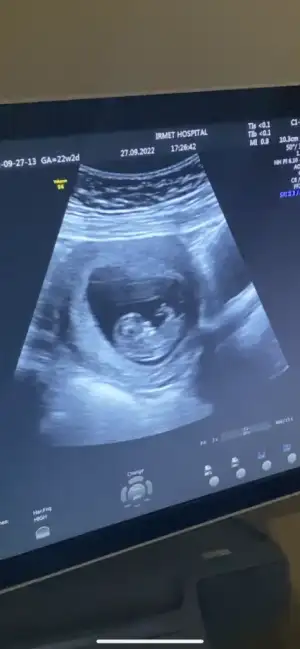

Canım ultrasonda niye 22 hafta 2 günlük yazıyor yanlış mı yazılmışBebişe nub a göre yorum yapabilecek var mı kızlarr aşırı merak ediyorum B BarbieveKen göreveebirde kalp atışı dk da 144 dedi araştırmalarıma göre 140 ın üstü kız yazıyor

ay öyle güzel oynuyordu ki pıtır pıtırdı eller ayakları

bence erkek ..benim de ultrasonda boyle görünüyodu irice.tahminimce erkektirNub u nasıl anlıyorsun net bir şekilde, bende intten cok baktim ama anlamıyorum, benimkinin burda nub belli mii B BarbieveKen